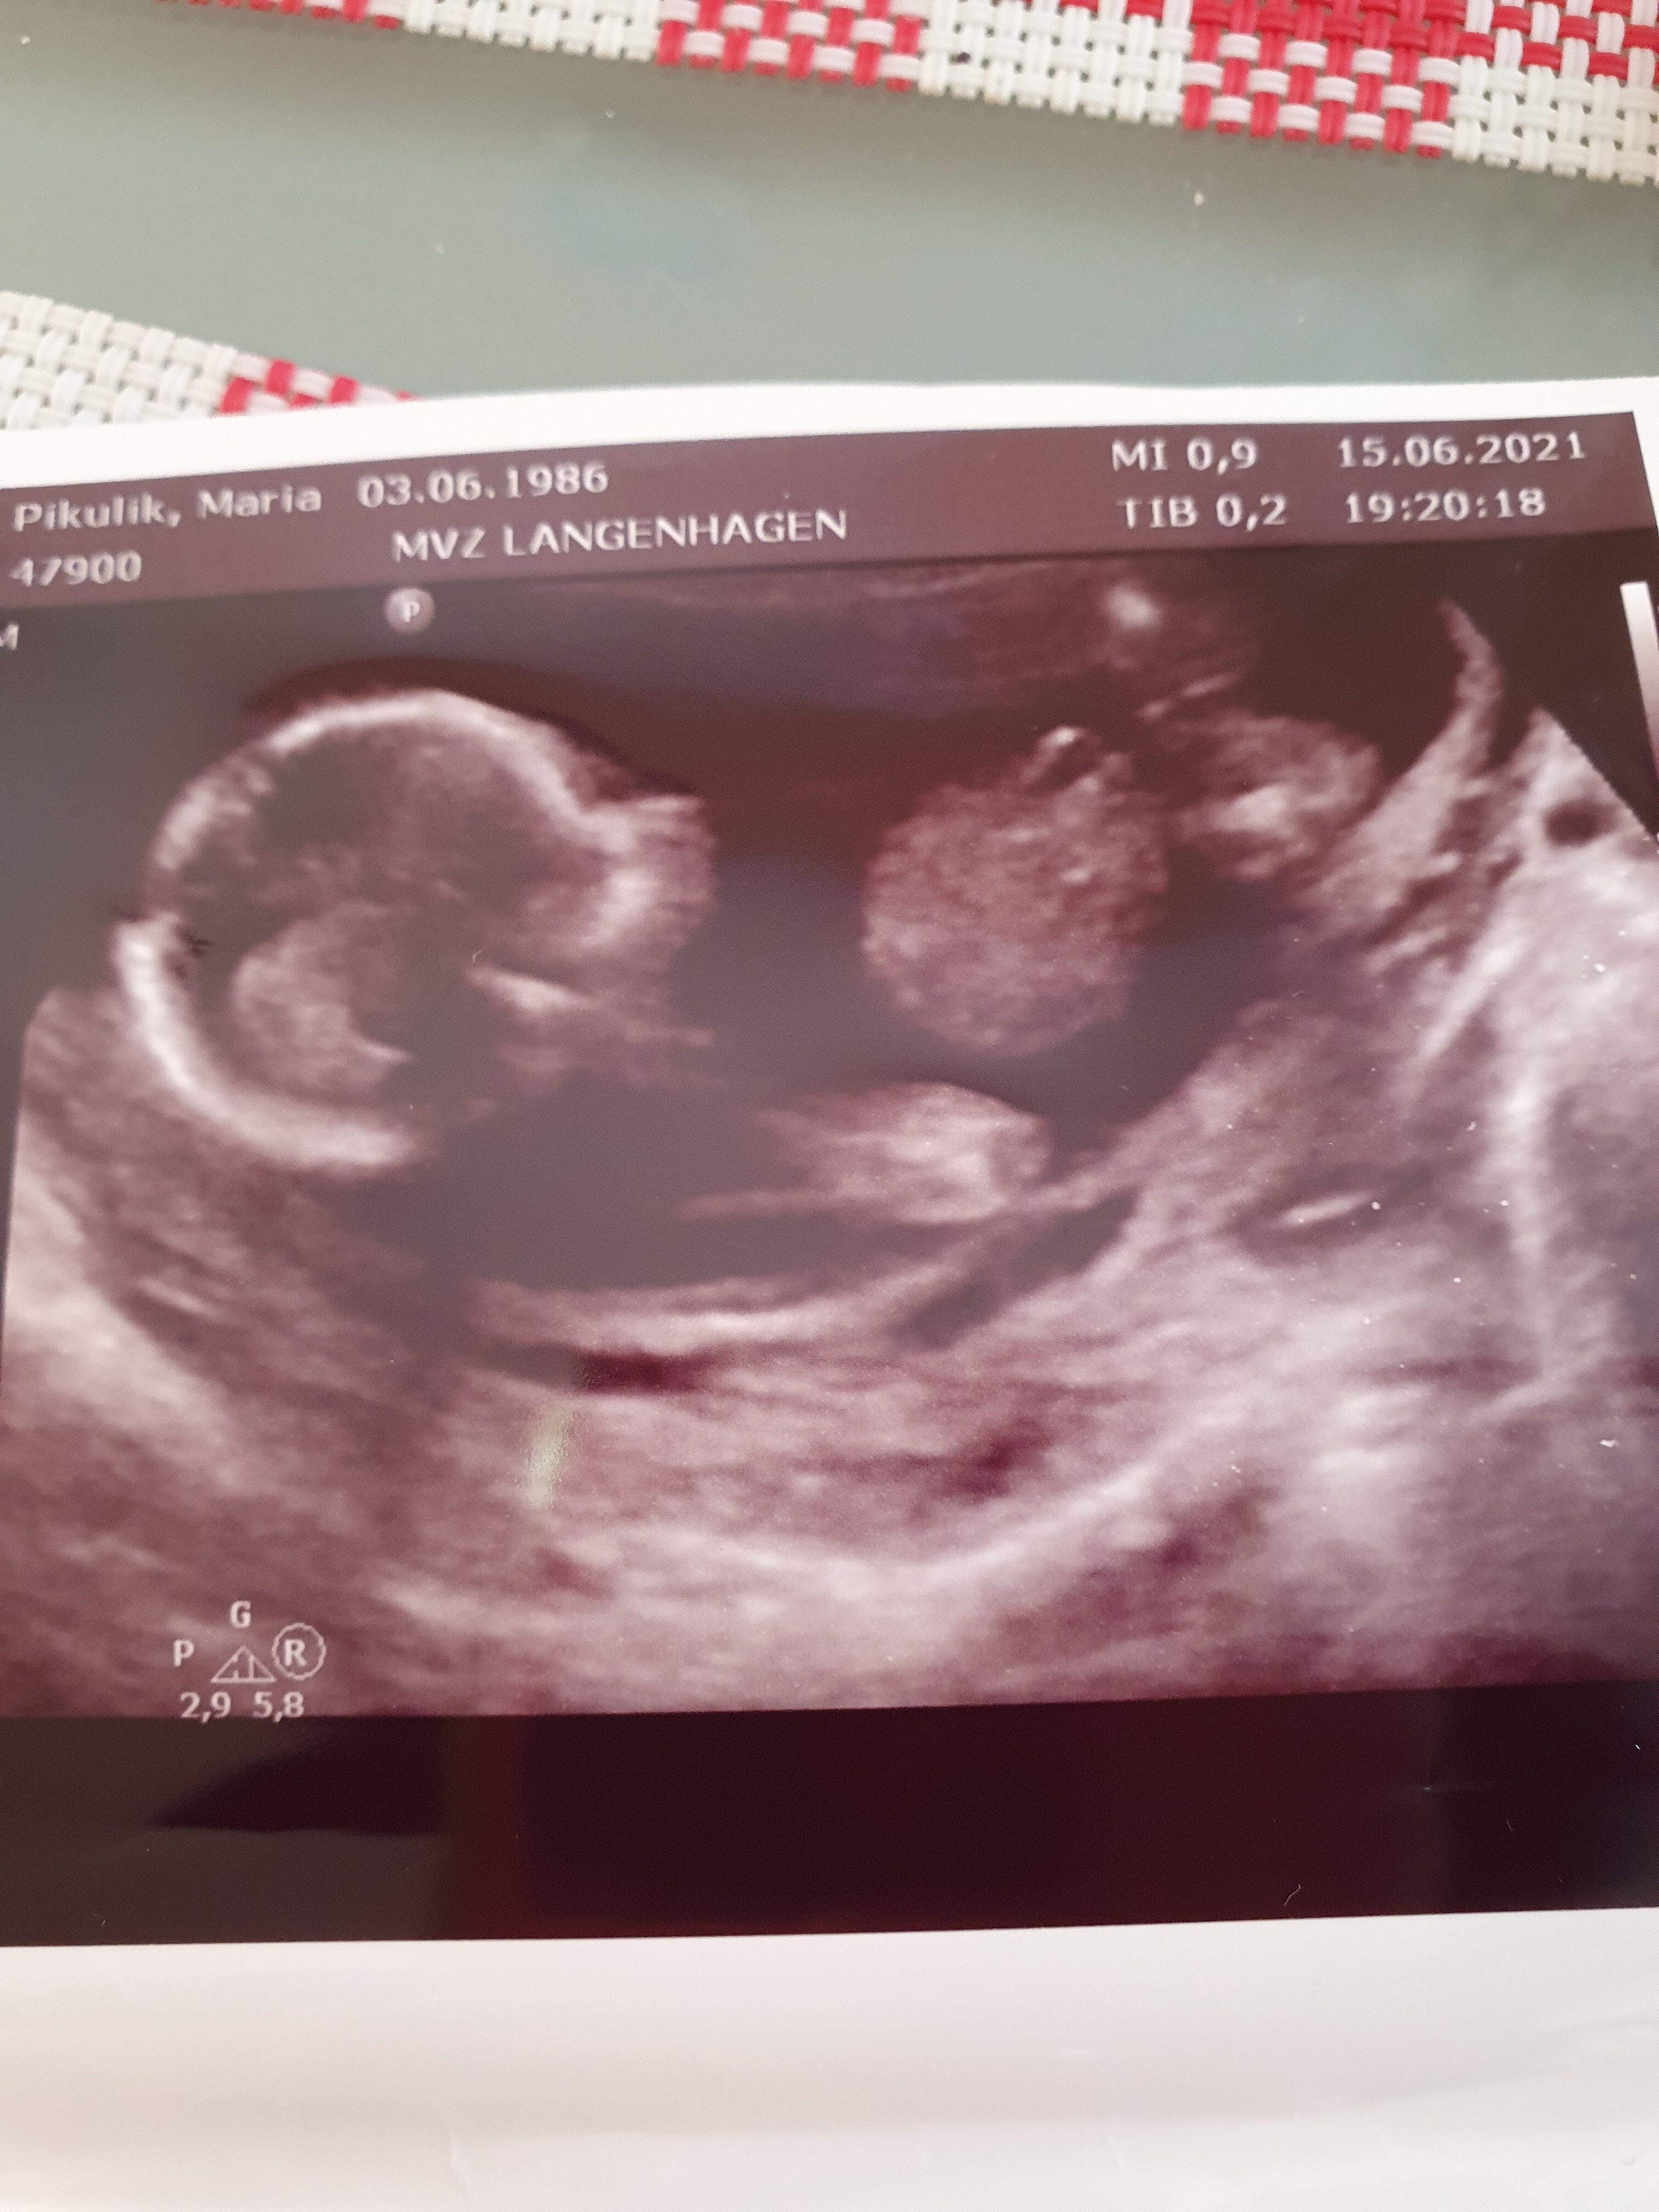

Witam wszystkich😘

Czy mozna cos tu dojrzec? Prosze o ocene🤗

Załączniki

• 162391079995058163150998813343.jpg

162391079995058163150998813343.jpg

1,3 MB · Wyświetleń: 222

• 1623910841266111468245772657511.jpg

1623910841266111468245772657511.jpg

1,3 MB · Wyświetleń: 235